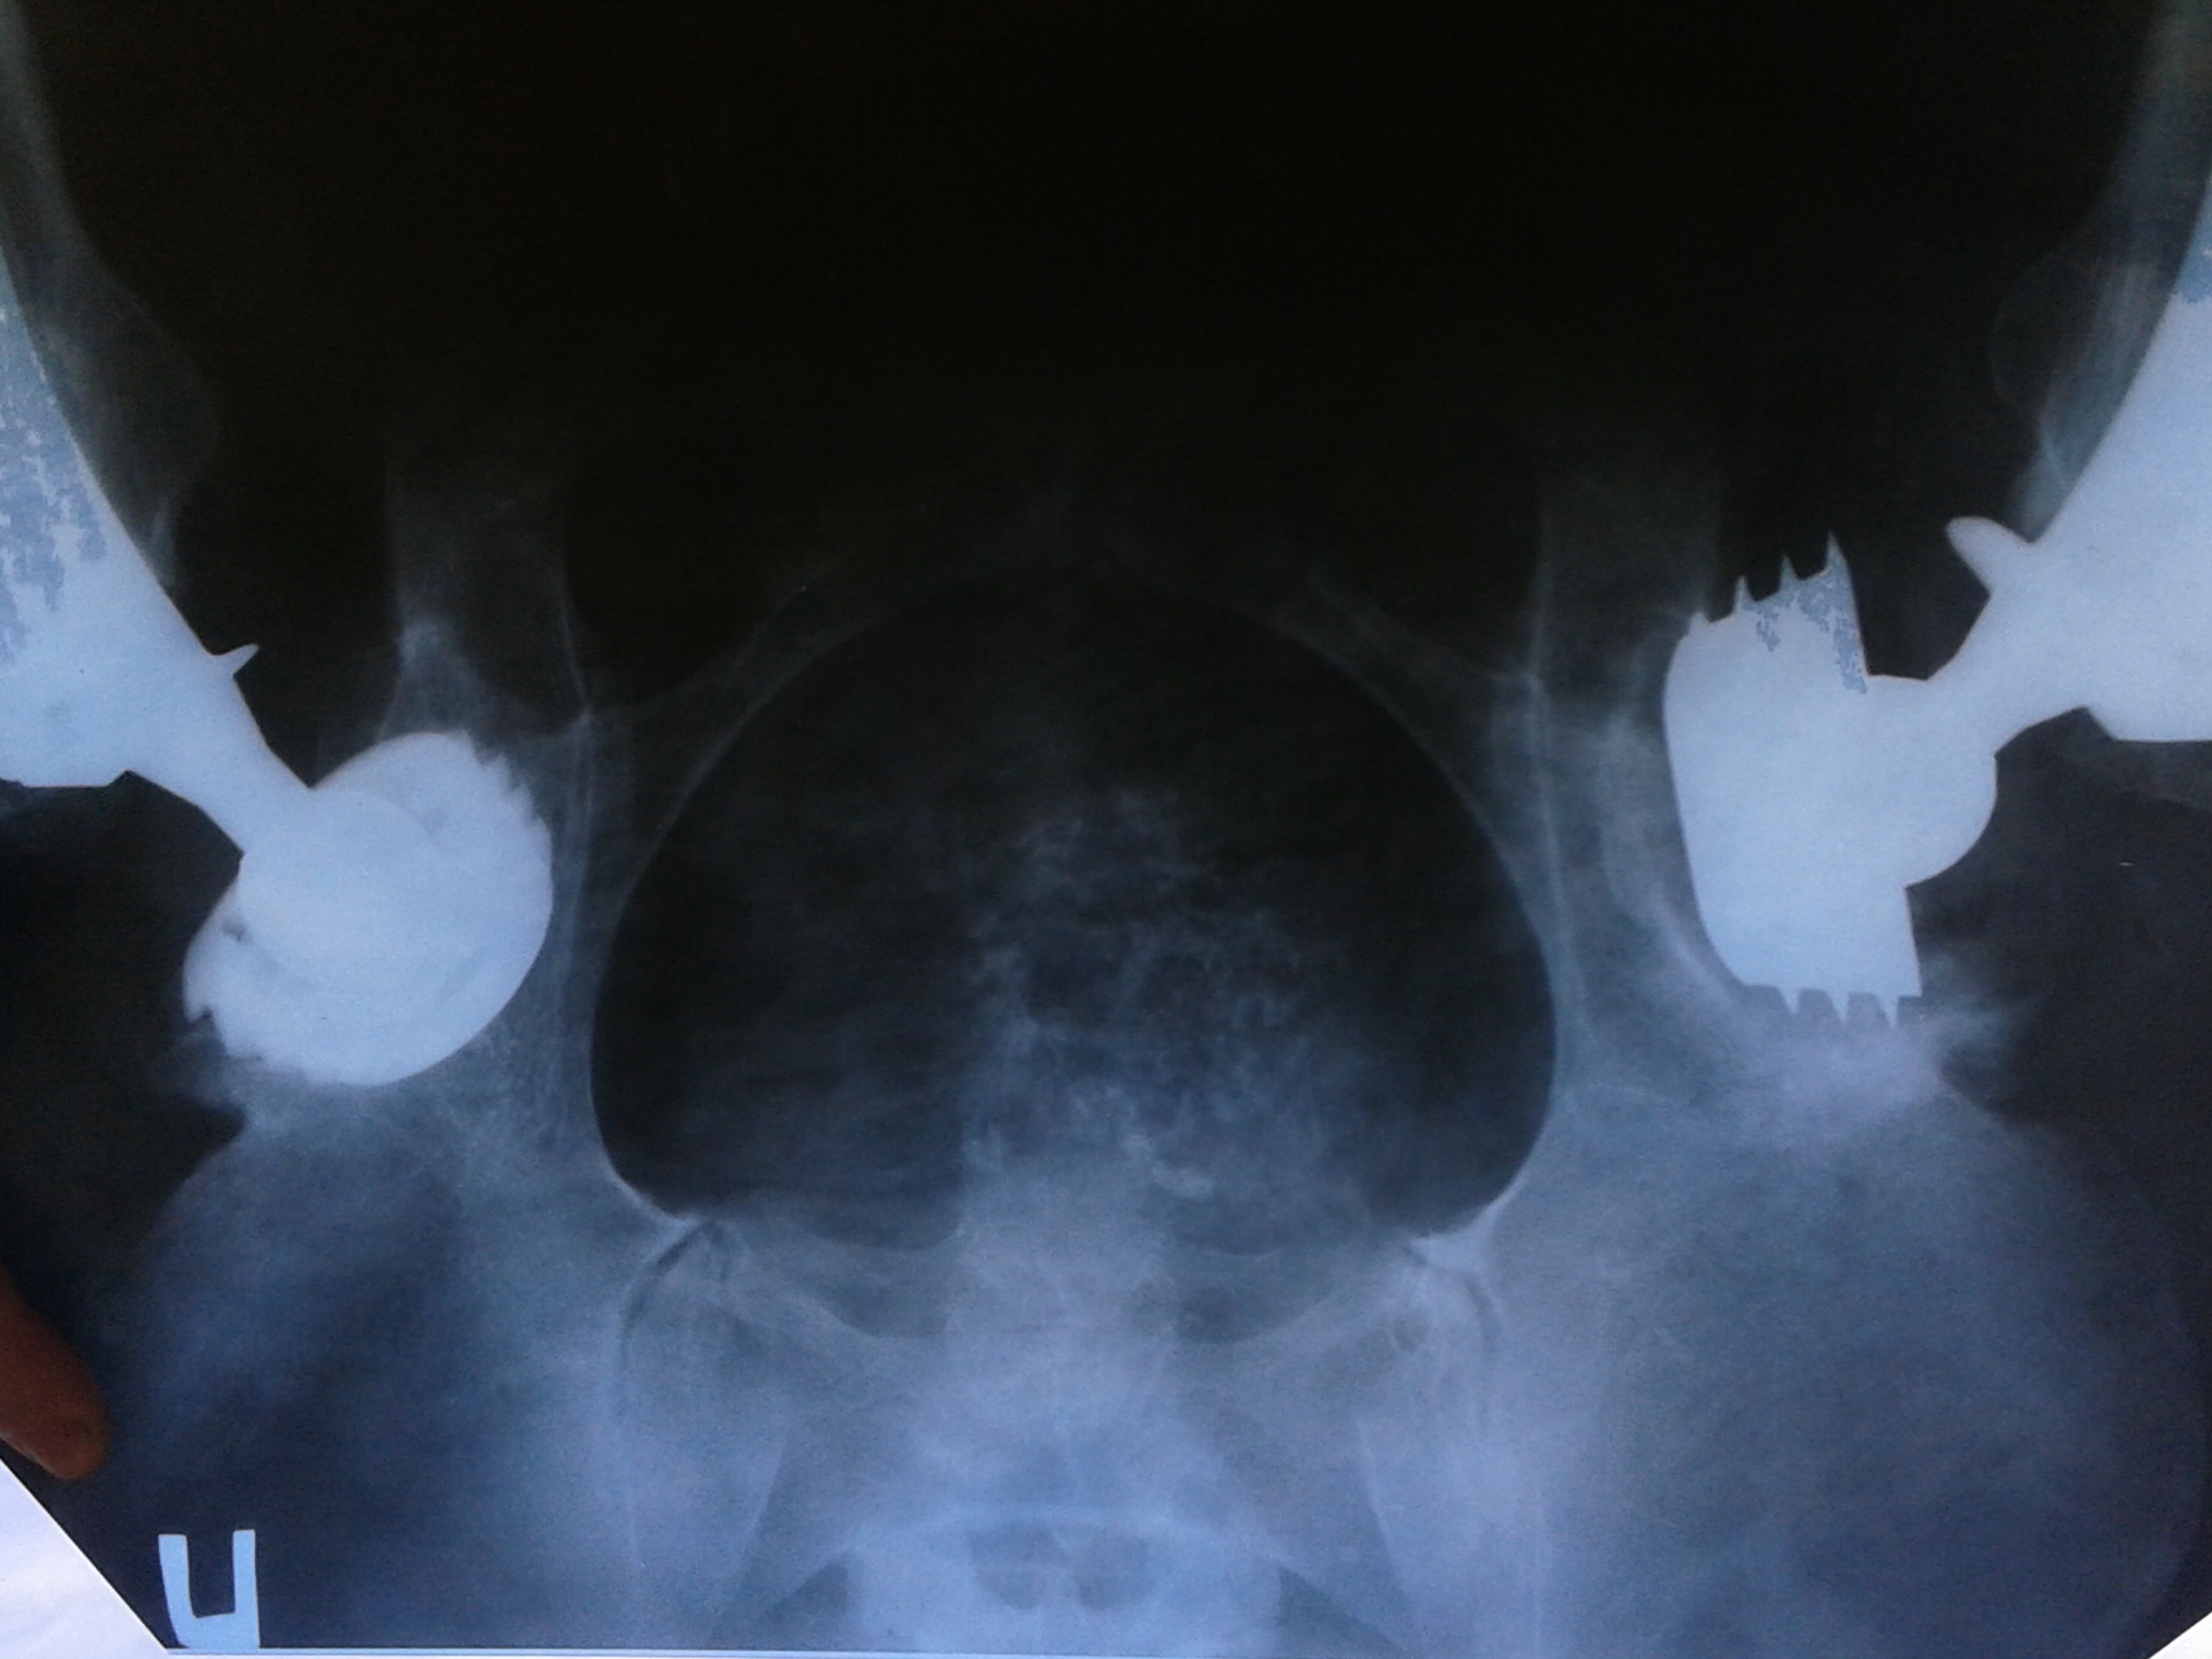

Диагноз: Двухсторонний диспластический коксартроз ІІІ- ІV степени.

Я старалась изо всех сил: операция, лекарства, массажи, снова операция, снова реабилитация, снова лекарства и больницы. В 2008 году – у меня была операция по замене правого тазобедренного сустава. А в 2011 году боли усилились, возникла необходимость провести следующую операцию по замене теперь уже левого сустава. Но как-то всё неудачно, состояние здоровья только ухудшилось, и теперь новая беда: срочно требуется ревизионное эндопротезирование левого тазобедренного сустава.